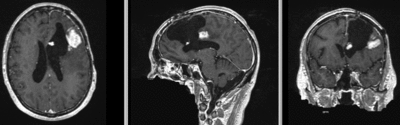

this is the fixed reference image. All images are aligned into this space lleft this is the moving image. The transform is calculated by matching this to the reference image

fixed image/target moving image

• reference/fixed : T1 SPGR , 1x1x1 mm voxel size, 256x256x176 ,sagittal

• moving: T1 SPGR , 1x1x1 mm voxel size, 256x256x176 ,sagittal